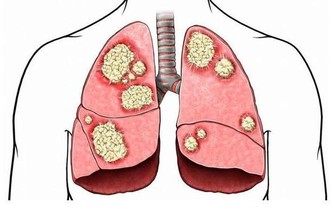

1、腐腥臭是肺癌

當患上肺部疾病時比如肺部感染肺炎、氣管炎、肺癌都會引起口臭,主要是因為患者的肺部積攢了大量粘液所引起的口臭。肺膿腫的患者一般會伴隨腐酸性口臭味,同時也會伴有膿性痰以及發燒,只有去醫院做胸片檢查才能夠確診。支氣管擴張以及肺結核患者會出現血腥味的口臭,晚期肺癌患者會有腐腥口臭味。